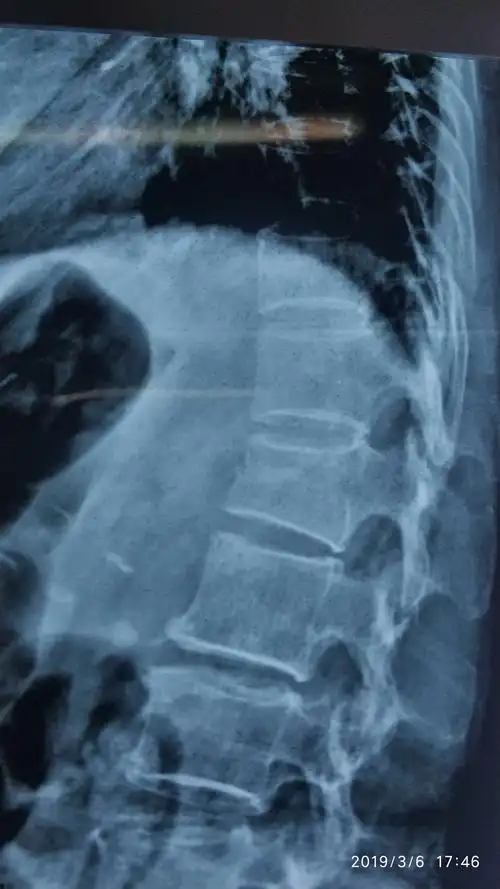

术前dr示腰1椎体压缩骨折

腰椎压缩性骨折新鲜

来我院影像检查提示:腰1椎体压缩性骨折.

腰椎平片提示腰1椎体前缘压缩有二分之一,侧位片非常明显,且腰椎ct

术前x线l1压缩性骨折

腰1椎体压缩骨折